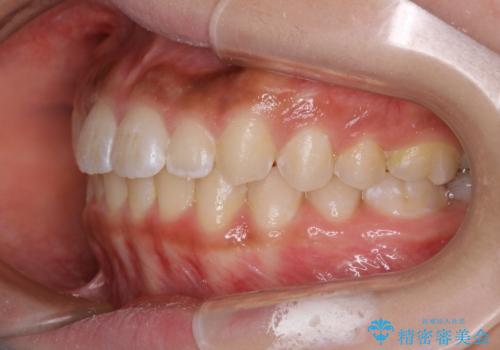

短期間ですきっ歯を改善:インビザラインLite

- 上の歯がすきっ歯なのと、歯が出ている気がするとご相談にいらした方です。

奥歯の噛み合わせに大きな問題がなく、患者様のご希望もあったため、前歯部メインで治療するインビザラインLiteで治療を行いました。

日常的に舌を突出する癖があったため、後戻り防止のために舌および口唇の筋機能訓練も合わせて行いました。

横顔のシルエットが改善し、口元もスッキリとなりました。

舌癖がある方は、歯を内側から押し出す力が日常的に働くため、矯正治療後も歯と歯の隙間が開いてしまうなどの後戻りのリスクが高いことが知られています。舌の正しいポジショニングやお口周りの筋肉のトレーニングを行うことで後戻りのリスクを減らすことが可能です。